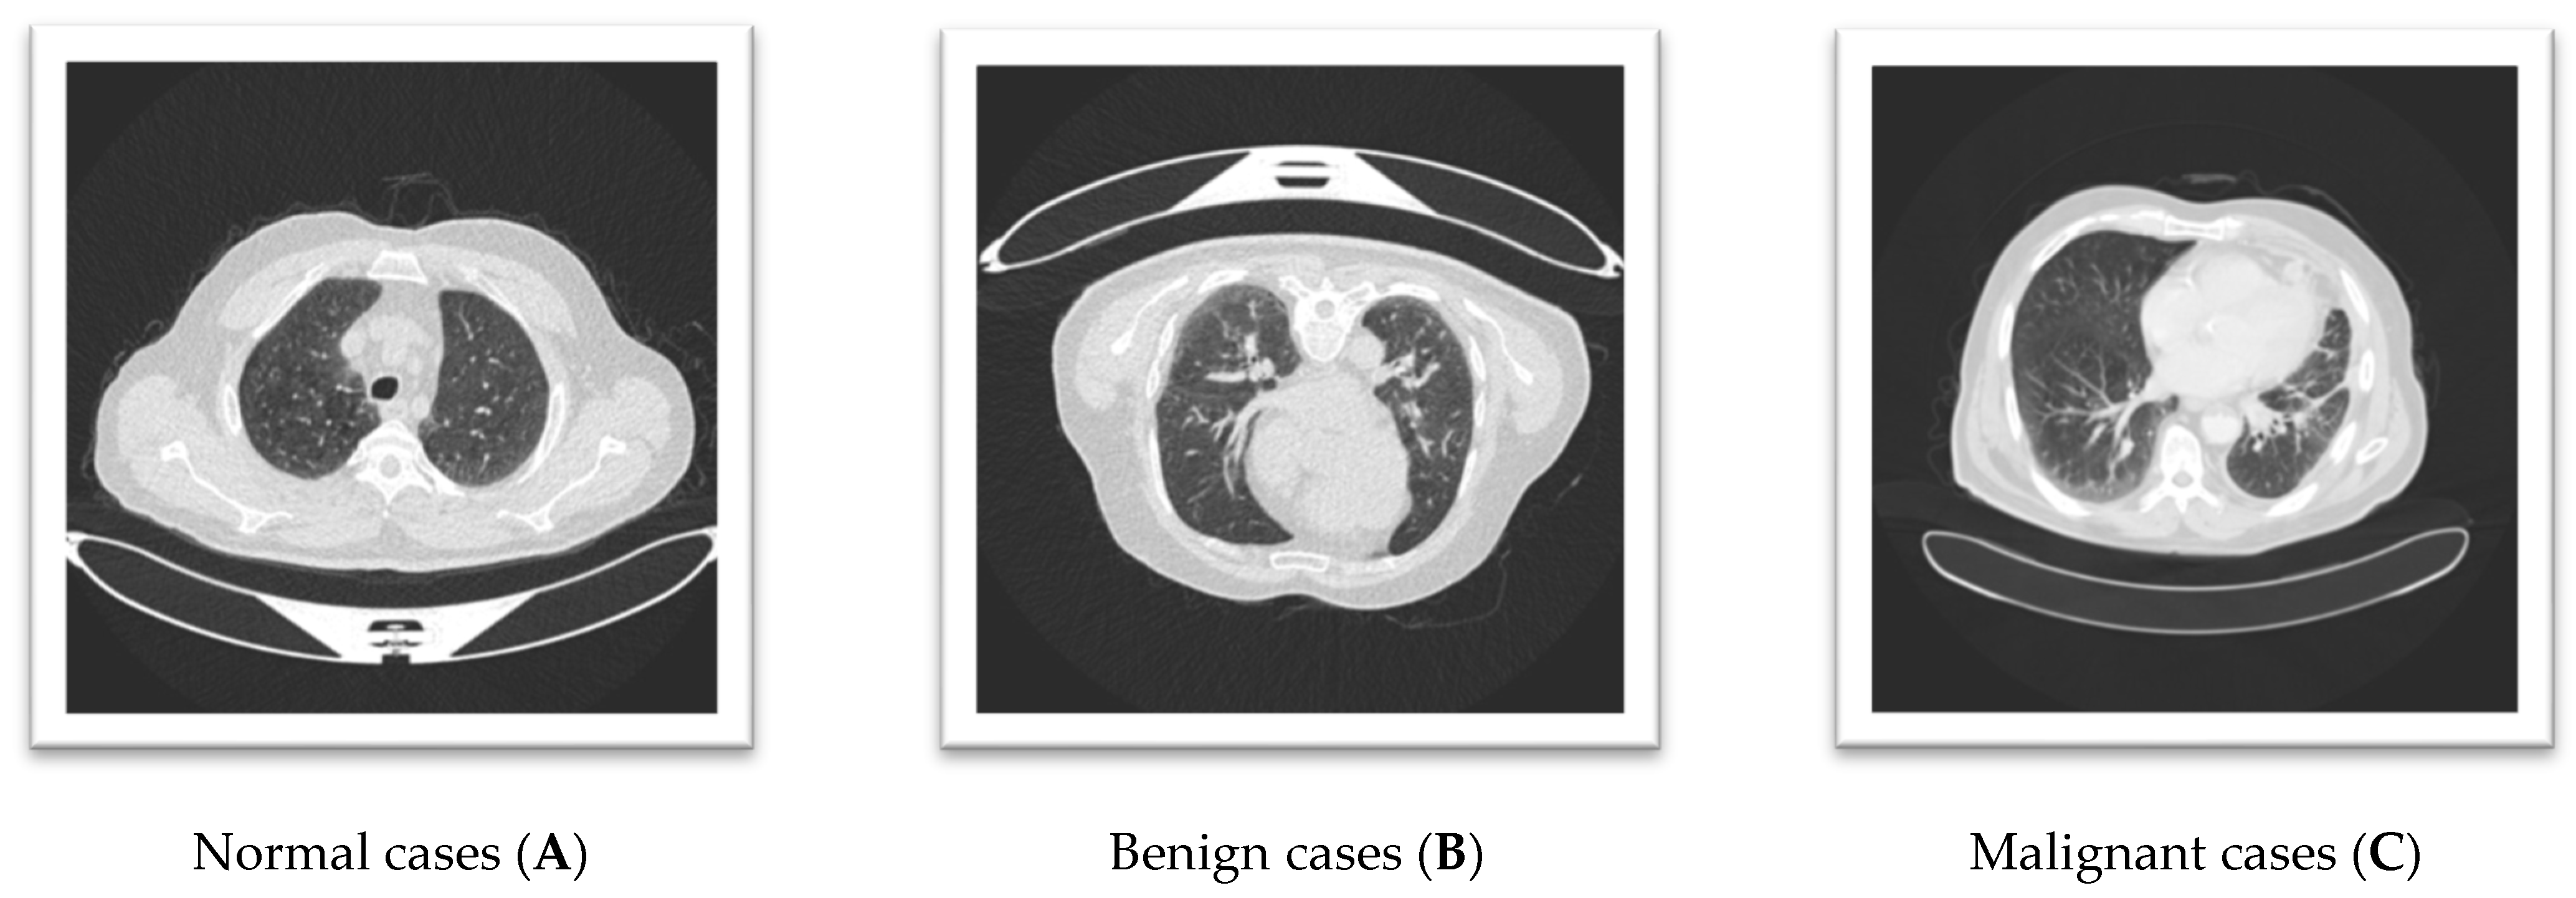

Figure 1 shows a lung CT scan image that reveals distinct findings for each case. Image A, representing a Normal case, shows a nodule or mass localized in the right lung, indicating a potential abnormality despite its classification as normal. Image B, classified as Benign, depicts clear lung fields with well-defined pulmonary vessels, consistent with non-pathological findings. Image C, labeled Malignant, exhibits interstitial changes or potential infiltrates in the lower lung fields, suggesting significant pathological alterations. These observations highlight the variability in CT scan presentations across different classifications, emphasizing the importance of accurate feature interpretation for reliable diagnosis.

Figure 1.

The three lung CT scan images.